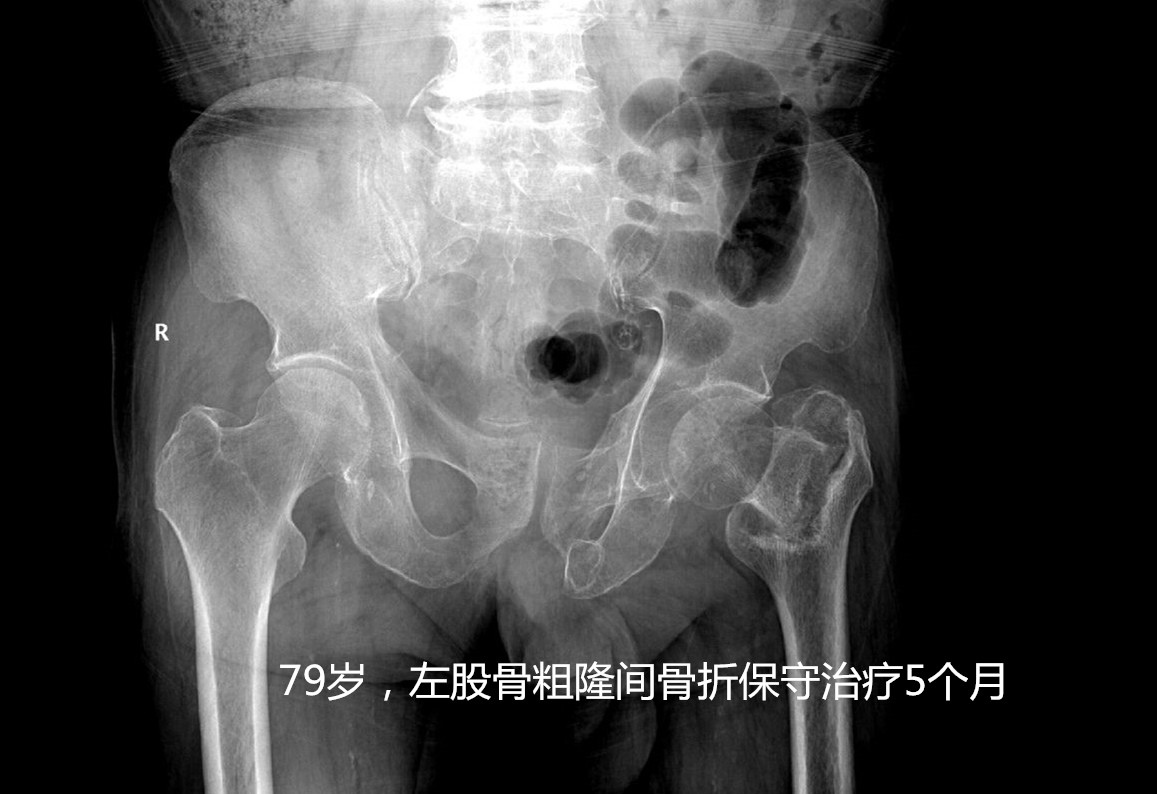

答案就是指 老年人髋部骨折 ,也就是东北话常说的“ 胯骨轴摔坏了 ”,包括股骨颈及粗隆间骨折。这个部位骨折后病人因轻微活动便会诱发较剧烈的疼痛,通常无法坐起、翻身困难,需长期卧床,只有一少部分骨折无移位或者骨折断端嵌插的病人,经2-3个月的卧床后出现骨折愈合后可能恢复行走功能,其余病人可能因骨折不愈合、畸形愈合等丧失行走功能。长期卧床面临着肺内感染、坠积性肺炎、褥疮、下肢静脉血栓、泌尿系感染等并发症, 据统计约50%的患者因卧床出现相关并发症在1年内死亡 ,所以被称作“人生最后一次骨折”。

• 对于老年高龄的股骨颈骨折患者,一般可能人工股骨头置换手术,手术时间短,术后1-2日病人可早期下床活动,降低卧床并发症,提高患者生活治疗。对于粗隆间骨折,可行PFNA或者人工股骨头置换手术。